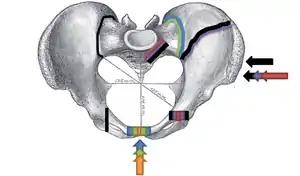

.png.webp)

Pelvic fractures are most commonly described using one of two classification systems. The different forces on the pelvis result in different fractures. Sometimes they are determined based on stability or instability.[8]

Young-Burgess classification

The Young-Burgess classification system is based on mechanism of injury: anteroposterior compression type I, II and III, lateral compression types I, II and III, and vertical shear,[5] or a combination of forces.

Lateral compression (LC) fractures involve transverse fractures of the pubic rami, either ipsilateral or contralateral to a posterior injury.

- Grade I – Associated sacral compression on side of impact

- Grade II – Associated posterior iliac ("crescent") fracture on side of impact

- Grade III – Associated contralateral sacroiliac joint injury

The most common force type, lateral compression (LC) forces, from side-impact automobile accidents and pedestrian injuries, can result in an internal rotation.[9] The superior and inferior pubic rami may fracture anteriorly, for example. Injuries from shear forces, like falls from above, can result in disruption of ligaments or bones. When multiple forces occur, it is called combined mechanical injury (CMI). The best imaging modality to use for this classification is probably a pelvic CT scan.

Open book fracture

One specific kind of pelvic fracture is known as an 'open book' fracture. This is often the result from a heavy impact to the groin (pubis), a common motorcycling accident injury. In this kind of injury, the left and right halves of the pelvis are separated at front and rear, the front opening more than the rear, i.e. like an open book that falls to the ground and splits in the middle. Depending on the severity, this may require surgical reconstruction before rehabilitation.[10] Forces from an anterior or posterior direction, like head-on car accidents, usually cause external rotation of the hemipelvis, an “open-book” injury. Open fractures have increased risk of infection and hemorrhaging from vessel injury, leading to higher mortality.[11]